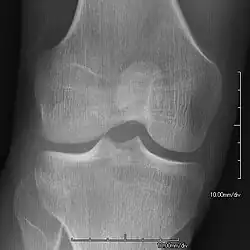

AP radiograph showing a hypoplastic patella in NPS

• Patellar involvement is present in approximately 75% of patients;[5] however, patellar aplasia occurs in only 20%.

• In instances in which the patellae are smaller or luxated, the knees may be unstable.

• The knee joint may appear square.